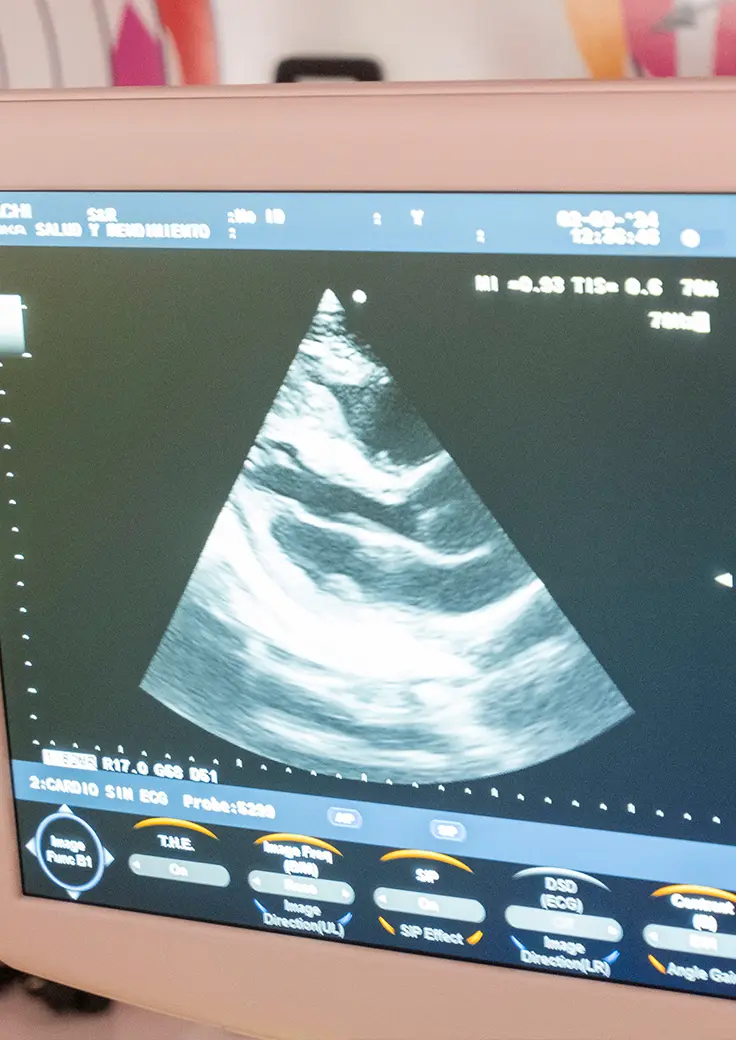

Ecocardiografía

Unidad de cardiología